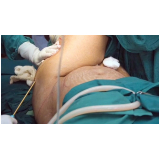

Lipoaspiração a Laser

Você merece a qualidade e comprometimento entregues pela equipe deste consultório médico e se neste momento está à procura de uma equipe que realize lipoaspiração a laser saiba que a FF Cirurgia Plástica disponibiliza de imediato este serviço para você!

Lipoaspiração a laser: atendimento eficiente e com qualidade que você sempre buscou!

Neste consultório médico você encontrará profissionais eficientes e com experiência de excelência. Usufrua de bom atendimento, através dos melhores preços do mercado e de assistência especializada sempre à sua disposição! Leve as suas dúvidas, converse com a equipe da FF Cirurgia Plástica. Contrate bons serviços e sinta-se mais seguro para cuidar da saúde.